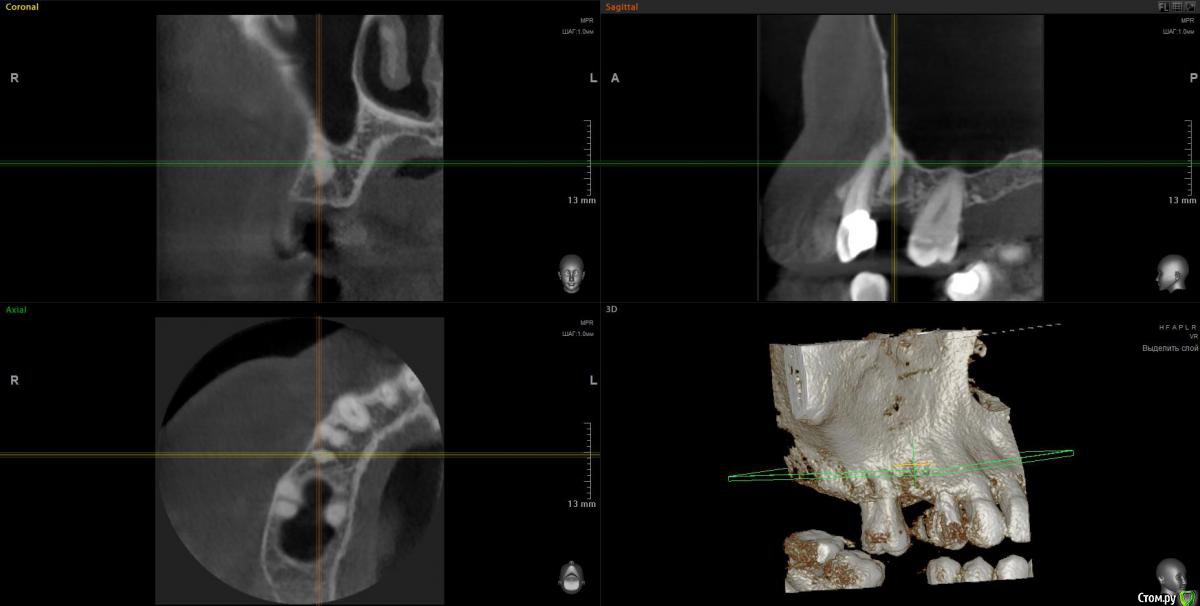

Elena64 Опубликовано 10 мая, 2018 Поделиться Опубликовано 10 мая, 2018 Добрый день!Удалили зуб пятерку справа10 месяцев назад,по словам хирурга,от зуба практически ничего не осталось,он был очень хрупкий.Долго не зарастала лунка,несколько раз обращалась к врачу,кот.удалял,но он проблемы не видел,вроде как заживает нормально,пришлось пропить аб через 1.5 месяца после удаления,т.к. предстояла поездка ,которую нельзя было отменить.На фоне приема аб цефтриаксон лунка начала подживать и общее самочувствие улучшилось,но ненадолго ,через какое то время опять стало печь десну и небо верхней челюсти,привкус горьковатый ,держится небольшая температура,дурнота.Лечилась в лор отделении ,т.к. постоянно стекает по задней стенке слизь,боли в носу,снова аб.После отмены аб на месте удаленной несколько лет назад верхней семерки начала на десне со стороны языка вылазить кость,обратилась в ч/л хирургию обл. больницы,прооперировали с диагнозом экзостоз.На некоторое время опять стало легче.Сейчас все по новой:жжет и печет десну и небо справа в месте удаленного зуба и соседней шестерки,свища вроде бы не видно,лунка удаленного зуба с виду здорова,но там есть болезненность при нажатии или что то не нее попадает, постоянно чувствую привкус оч.неприятный во рту,полный рот слизи,тошнота,к середине дня поднимается небольшая температура 37.2,по задней стенке течет.Сейчас на десне со стороны языка напухло,как будто что--то оттекло и стало легче.Сделала клкт этой зоны,обращалась к хирургу,который удалял зуб,говорит что хирургического там ничего нет,а то , что другие врачи принимают за неудаленный корень,то это участок склероза и он беспокойства приносить не может. Прошу посмотреть что не так по Вашему мнению,вот ссылка на клкт:https://cloud.mail.ru/public/A2Vt/Y2cPqDr1M .Заранее благодарна,Елена Ссылка на комментарий

Elena64 Опубликовано 14 мая, 2018 Автор Поделиться Опубликовано 14 мая, 2018 Добрый вечер!Получила сегодня описание из Пикассо : 1.6 зуб. Коронковая часть: восстановлена нерентгеноконтрастной пломбой. Количество корней/каналов: три корня/четыре канала; На дистальной поверхности определяются твердые зубные отложения. В мезиально-щечном корне два канала. Периодонтальное пространство не расширено; Твердая пластинка альвеолы сохранена (Рис.2). В области отсутствующего 1.5 зуба — состояние после удаления. В лунке определяется фрагмент корня с ровным, четким контуром, раз- мерами 3.5х2,4х8,8 мм. Периодонтальное пространство не прослеживается.ДИАГНОСТИЧЕСКОЕ ЗАКЛЮЧЕНИЕ: Частичное отсутствие зубов. Фрагмент корня в лунке отсутствующего 1.5 зуба. Ссылка на комментарий